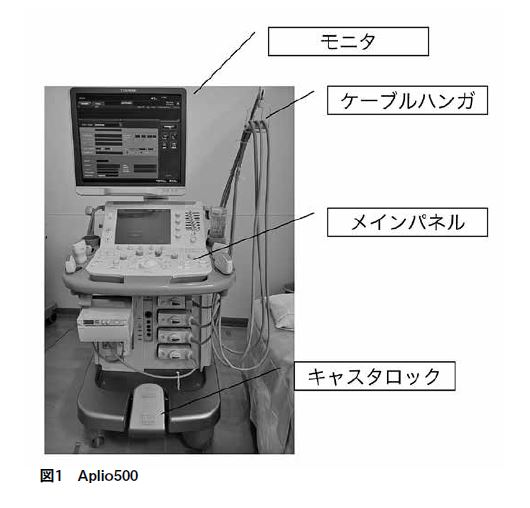

私の勤務している東京臨海病院では、専門外来は別として心臓と一部血管系以外の超音波検査は放射線科で行っている。放射線科では、2014年に購入したキヤノンメディカルシステムズ株式会社製超音波画像診断装置Aplio500(TUS-A500)と乳腺専用に使用しているさらに古参のキヤノンメディカルシステムズ株式会社製超音波画像診断装置Xario XG(SSA-680A)の2台が稼働している。

1年間で腹部領域・表在領域・血管領域合わせて4000件以上の検査をこなす相棒「Aplio500」が私のお気に入りの装置である(図1)。

モニタは、上下左右に可動し固定ができる。メインパネルも高さと前後左右に可動させ固定することができ、モニタと合わせて調整することで、プローブ走査する時の不自然な姿勢の負担を軽減することができる。プローブケーブルを掛けるケーブルハンガは、購入後にアーム(正規品)を付けて操作しやすくした。

下肢血管など走査範囲が長い場合、走査しながら装置を移動することも多々ある。以前の装置には、キャスタ一つ一つにストッパーがついていたが、Aplio500には、キャスタロック一か所で全てのキャスタの解除と固定ができる。また、ストッパーの角度で進行方向だけの解除を行うこともでき検査中の移動が楽になった。